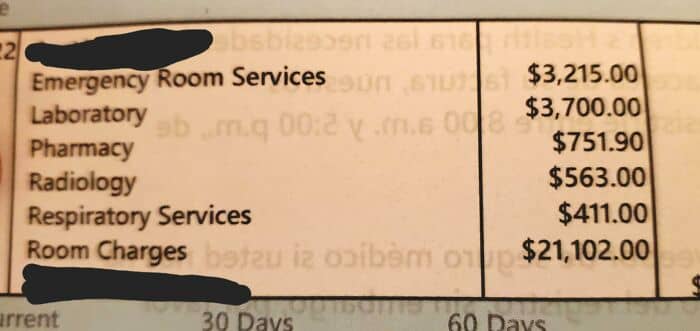

#85 3 Days In The Hospital